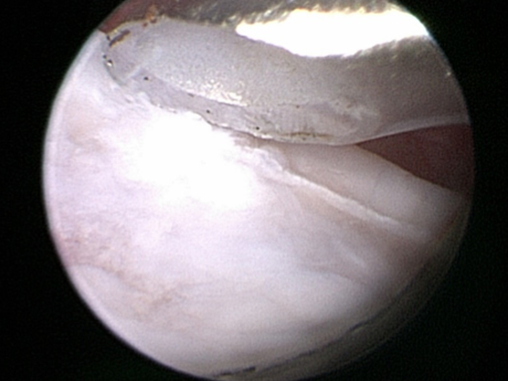

- Osteocondritis Dissecans (OCD). This is a condition in young large breed dogs and results in a flap of cartilage and bone coming free from the back of the humerus. Removal of this flap by arthroscopy or arthrotomy will help settle the problem but there will always be a defect in the joint surface. In most cases this is not a clinical problem but in some where the defect is very large it can be a problem. In cases that have large lesions seen on CT we may suggest resurfacing with a synthetic plug inserted in to the OCD lesion. This is called a SynACART and does require a fairly large exposure and open surgery.